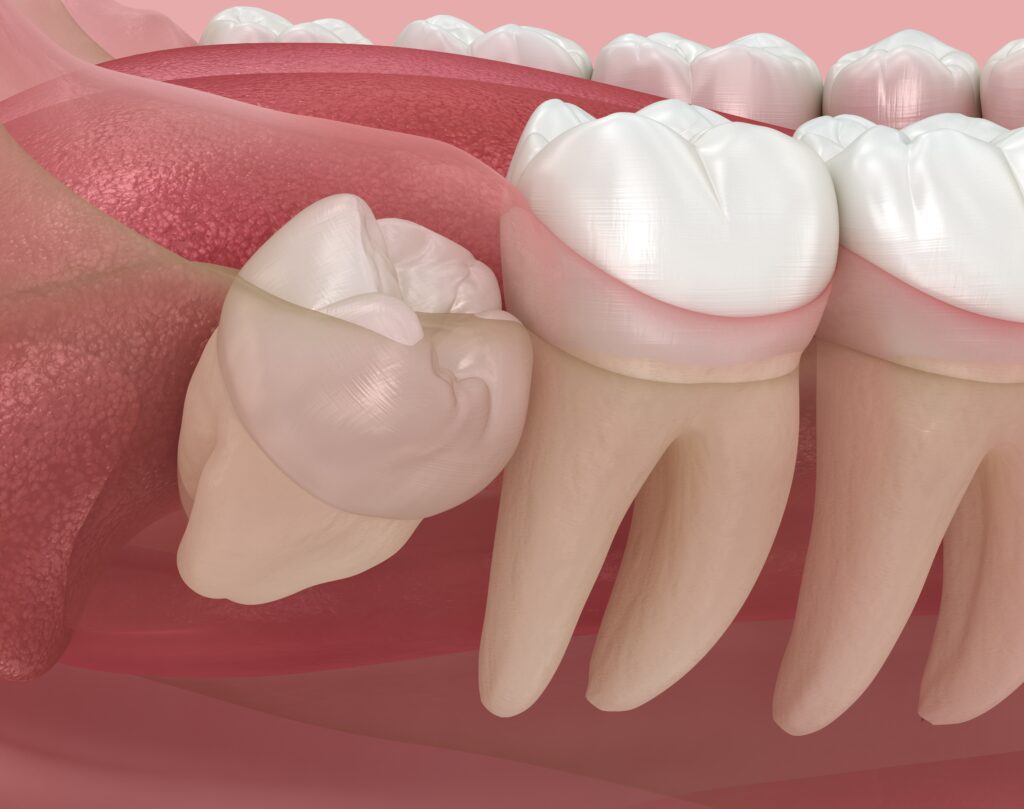

사랑니는 보통 10대 후반에서

20대 초반 사이에 맹출하는

세 번째 어금니를 의미합니다.

그러나 현실적으로는 공간 부족이나

비정상적인 맹출 방향으로 인해

문제를 일으키는 사례가 많습니다.

<앞 치아에 영향을 주는 경우>

매복된 사랑니가 앞쪽 어금니를

밀어내는 방향으로 자라는 경우

문제가 됩니다.

지속적인 압력이 가해지면

인접 치아 뿌리에 손상이 생기거나

치열이 틀어질 가능성이 있는데요.